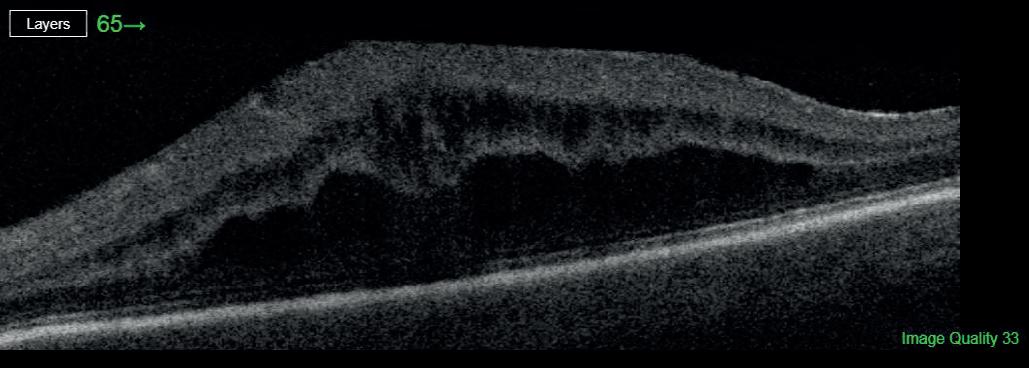

Most astronauts experience changes to the structures of their eyes and brains while in space flight, including swelling at the back of the eye called optic disc oedema (ODE).

The size of effects and time of onset of ODE varies widely between individuals. While changes tend to be reversed when crew members return to Earth, there are concerns that extended missions, such as those being proposed to the moon and Mars, could increase the risk of permanent vision problems.

US-based researchers analysed data on 31 astronauts who spent six to 12 months on the International Space Station. They found that 23 of the astronauts developed signs of ODE. Average total retinal thickness increased from a pre-flight average of 392.0μm to 430.2μm after around 150 days in space.

It has previously been suggested that those with a small or non-existent optic cup, an area at the centre of the optic disc, are more at risk of developing ODE during spaceflight (Stenger et al, 2019).

In the new study, published in JAMA Ophthalmology, the researchers found that astronauts with small, shallow and narrow optic cups pre-flight experienced larger increases in retinal thickness while in space. No other pre-flight ocular measures were associated with ODE.

Only six women took part in the study, so it is limited in its applicability to female astronauts. It was also not possible for in-flight measurements to be collected after the same number of days, and the length of time since participants had taken part in previous space missions was not considered.

The findings, nonetheless, support the idea that astronauts with smaller optic cups may benefit from increased monitoring and use of countermeasures. bit.ly/3igZr70